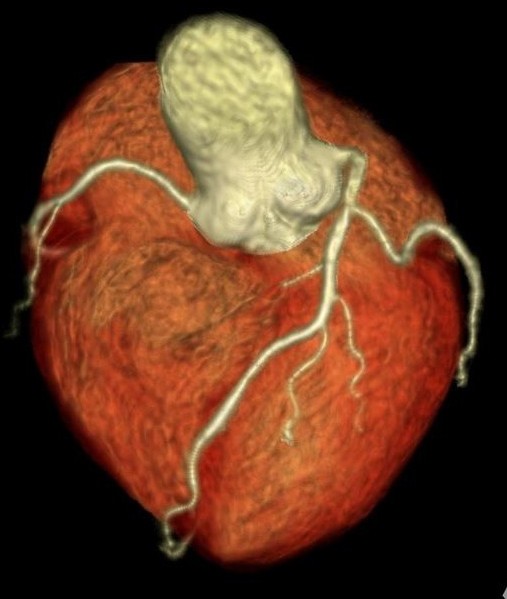

冠動脈MRA検査

『冠動脈VR画像』

この検査は、被ばくもなく、造影剤を使わずに冠動脈を描出することができる画期的な診断方法です。

狭心症や心筋梗塞など、年々増えている「冠動脈疾患」。冠動脈MRA検査により、カテーテルによる冠動脈検査を行わずに冠動脈の狭いところを見つけること出来るようになり、心筋梗塞や突然死を未然に防ぐことに貢献しています。